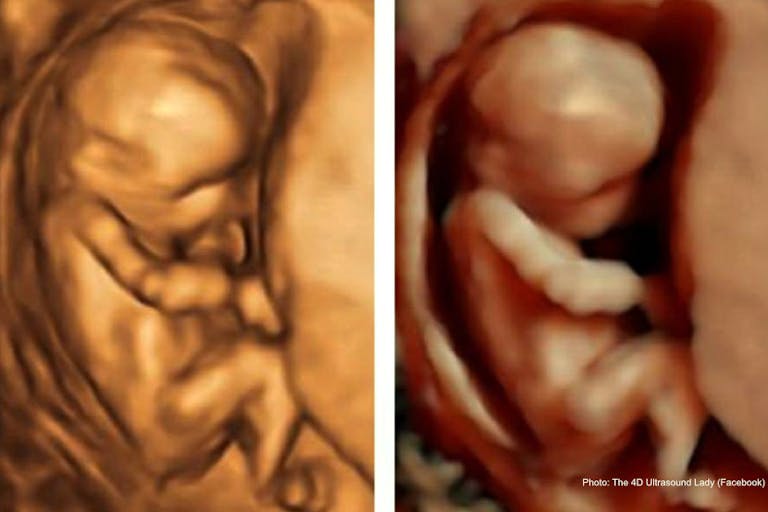

A prenatal development bill has passed in Indiana and is headed to the desk of Gov. Mike Braun. It requires that students in sexual education classes view human prenatal development videos as part of their curriculum — both an actual ultrasound and an animated rendering. While Indiana is one of many states working to enact such laws, there has been pushback from abortion supporters and inaccurate reporting regarding the bill.

… provide an in-person presentation on human growth and development during pregnancy that is medically accurate and age appropriate and includes the following: (A) A high definition ultrasound video, at least three (3) minutes in duration, showing the development of the brain, heart, sex organs, and other vital organs in early fetal development. (B) A high quality computer generated rendering or animation showing the process of fertilization and each stage of fetal development inside the uterus, noting significant markers in cell growth and organ development for every week of pregnancy from fertilization to birth.